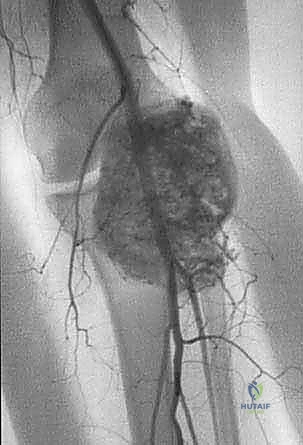

- الرنين المغناطيسي (MRI): هو المعيار الذهبي (Gold Standard) لتقييم الأورام. يوضح بدقة امتداد الورم في النخاع العظمي والأنسجة الرخوة، وعلاقته بالأعصاب والأوعية الدموية.

- الأشعة المقطعية (CT Scan): ضرورية لتقييم القشرة العظمية والتكلسات داخل الورم، وللبحث عن أي انتشار في الرئتين.

يعتمد الأستاذ الدكتور محمد هطيف على دراسة هذه الصور الإشعاعية شخصياً قبل تحديد مسار إبرة الخزعة، لضمان عدم تلويث الحجرات العضلية السليمة (Compartments).

لضمان أخذ العينة من الجزء الأكثر تمثيلاً للورم وتجنب المناطق الميتة (Necrotic areas)، يستخدم الدكتور هطيف جهاز الأشعة المقطعية أو جهاز القوس المفلور (C-arm) لتوجيه الإبرة في الوقت الفعلي.